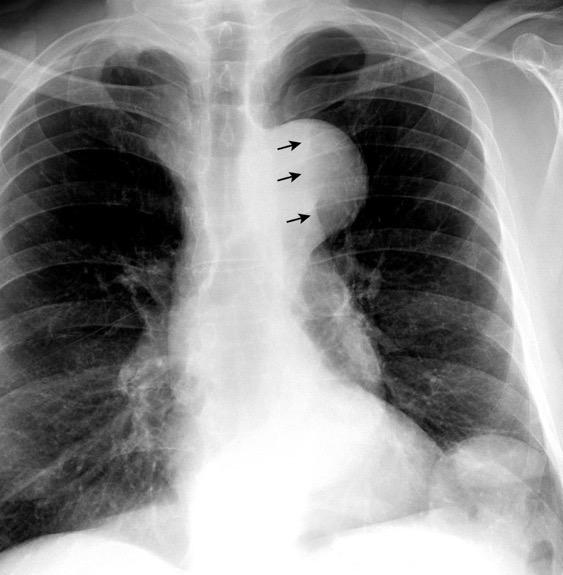

Síntomas y signos que se producen con la obstrucción total o parcial de la vena cava superior

Causas Malignas +/- 90-95%

Ca. Broncogénico (80-85%)

Linfoma No Hodgkin (15%)

Catéteres, shunts y marcapasos…23%

T. Mediastínico. Bocio

Fibrosis Idiopática

Tb, Histoplasmosis, Actinomicosis, Sarcoidosis

Carcinoma microcítico con síndrome de VCS

Grupos:

1. Obstrucción por encima de la V Ácigos. (La sangre llega al corazón a través de ella)

2. Obstrucción con participación de la V. Ácigos. (La sangre utiliza otras alternativas para llegar al corazón vía VCI).

Participación de la V. Ácigos como vía principal para llegar a la VCI.

Visible: 88%